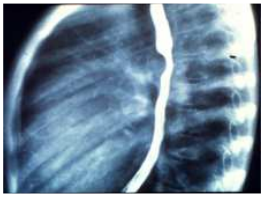

76.6歲女童,偶然發現胸部X光異常,胸部影像如圖,最可能的診斷為下列何者? (A)心臟腫瘤 (B)神經性腫瘤(neurogenic tumor) (C)橫膈疝脫(diaphragmatic hernia) (D)右肺中葉肺炎